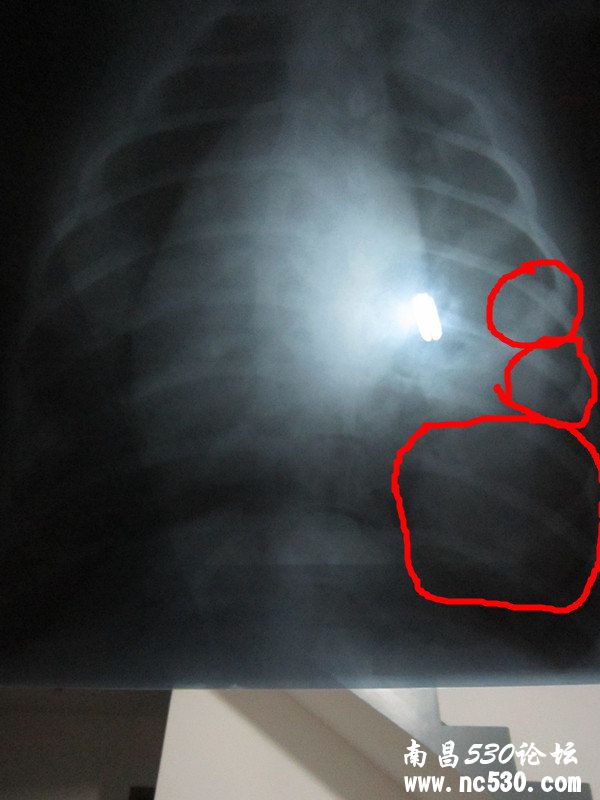

今天带狗狗去医院了,检查的结果是,鼻梁骨上增生,鼻道里面也长了东西,现在病菌已侵入肺部,肺部有好几个肿瘤,医生给的意见是没必要治疗,建议安乐死,请问还能给治好吗?我不想失去狗狗。